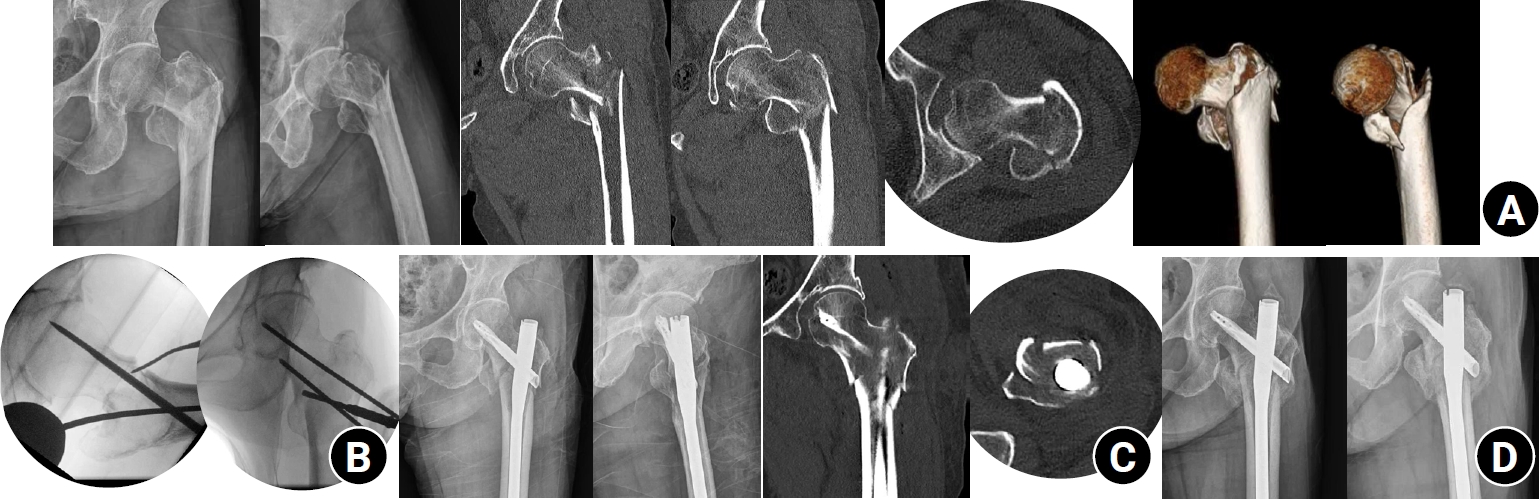

We retrospectively reviewed patients treated by a single surgeon in Korea between March 2022 and December 2024. Inclusion criteria were AO/OTA A1–A3 fractures, application of the leverage technique, preoperative and postoperative CT scans, and at least 6 months of follow-up. AMCS was assessed on CT as anterior support on axial images and medial support on coronal images, each graded as positive, neutral, or negative. Outcomes included time to union, union rate, change in neck-shaft angle, and treatment failure. Risk factors for failure were explored.

Of 273 patients screened, 53 met inclusion criteria. Follow-up was at least 6 months in all cases. Positive anterior support was achieved in 37 patients (69.8%) and positive medial support in 42 (79.2%). No patient demonstrated negative anterior support; one (1.9%) had negative medial support. Cortical support improved significantly after surgery (anterior P=0.026; medial P=0.001). Union occurred in 50 patients (96.2%) at 3.93±1.48 months. Mean varus change in neck-shaft angle at final follow-up was 1.75°±2.34°. Treatment failure occurred in three patients (5.7%). Anteromedial cortical breakage during follow-up differed between failure and non-failure groups (P=0.002), but regression identified no independent predictors. No technique-related complications were observed.